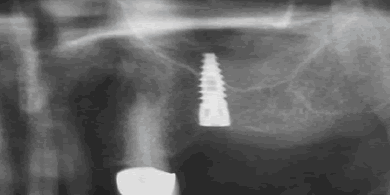

▲上顎洞にインプラントを突き出してしまった症例

下あごの時と同様に、必ず歯科用CT撮影を行い、上顎洞の立体的な位置を確認して埋入位置を検討し、安全な位置に埋入します。

また、手術の際にも、もしドリルの先が上顎洞に触れてしまっても、経験のある歯科医師ならそこでドリルの感触の違いに気づきますので上顎洞をドリルが突き抜けることはなく、痛みがないように安全に手術することが出来ます。